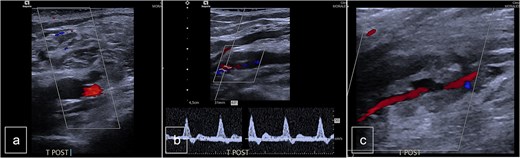

Surgical intervention was performed, consisting of open resection of the pseudoaneurysm at the proximal portion of the PTA, followed by patchoplasty with an autologous vein graft from the homolateral limb. The posterior tibial vein was ligated during the procedure (Fig. 3).

(a) Preoperative view. (b) Preoperative view. PTA after resection of the pseudoaneurysm and before the autologous patchoplasty.